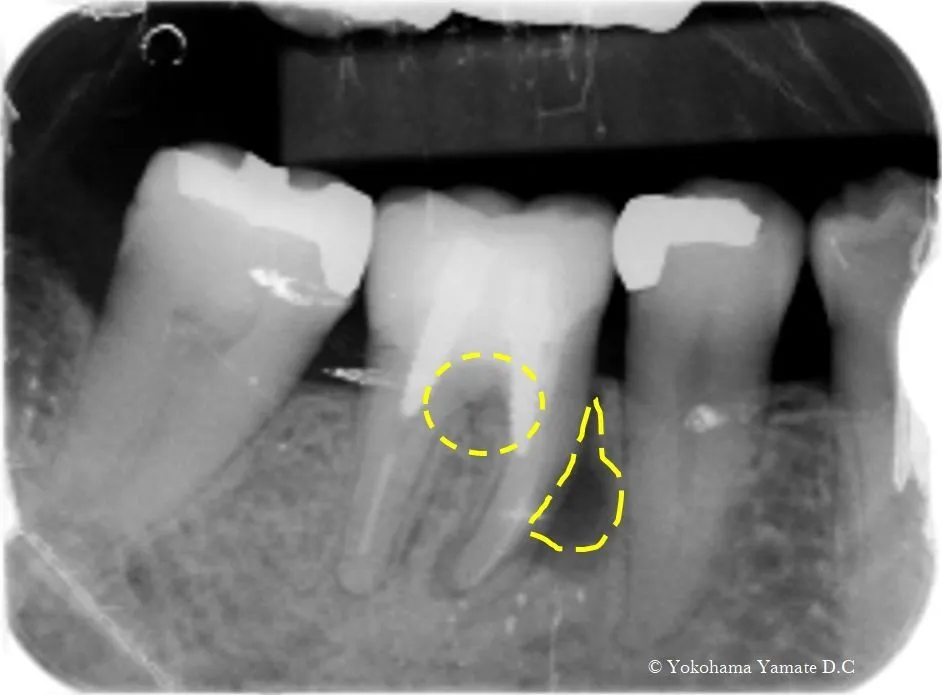

咬むと痛い歯肉に、おできがある舌側近心6mm骨吸収有ゾンデを入れてみた所骨がそこまで下がっていた。

歯周病原菌による感染層までゾンデを入れてレントゲン写真を撮る

術後6ヶ月での骨様組織の改善状態